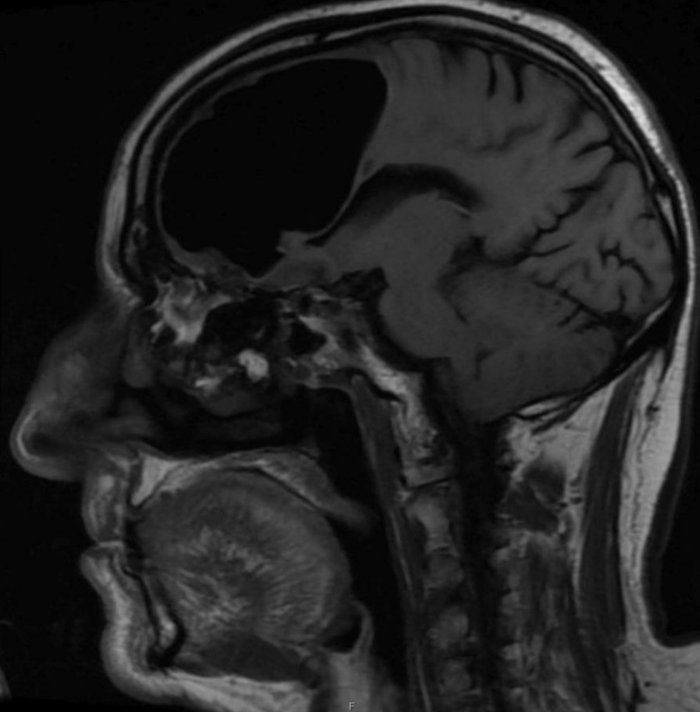

نتیجه سیتیاسکن گیجکننده بود، حفرهای بزرگ و سیاه به وسعت 9 سانتیمتر در لوب پیشانی سمت راست مرد دیده میشد. در مرحله بعدی مغز مرد با دستگاه MRI مورد بررسی قرار گرفت و پزشکان دریافتند ماده مغزی در جمجمه بیمار ناپدید نشدهاست، بلکه درون جمجمهاش حفرهای از هوا به نام پنوماتوکوئل ایجاد شدهبود که معمولا در بیمارانی دیده میشود که دچار آسیبدیدگی صورت یا عفونت تنفسی شدهاند یا در جمجمه آنها جراحی انجام شده است.